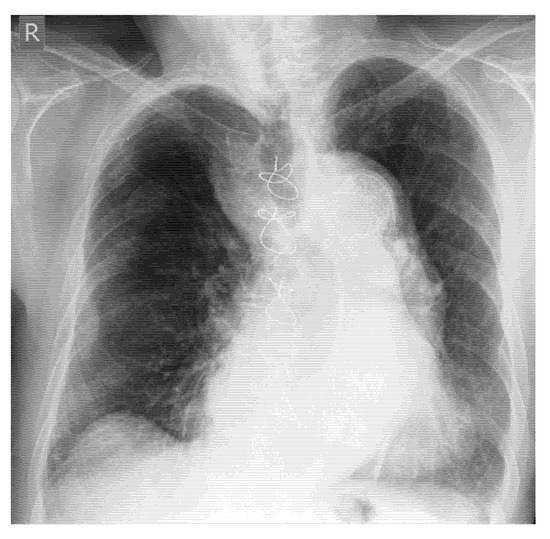

- Screening of fractures in the primary ATLS (Advanced Trauma Life Support) survey that are associated with or may cause life-threatening bleeding in polytrauma

- Recommendation 4: The E-FAST protocol, indicated for severely injured patients in shock, should be expanded to include fracture screening of long tubular bones and open-book fractures when the torso scan is negative for free fluid. This could identify hidden injuries and bleeding.

- In E-FAST, which is indicated for moderately to severely injured patients with shock, it can be expanded to fracture screening of long tubular bones and open-book fractures if the result of the torso scan is negative for free fluid.

- Yousefifard, M.; Baikpour, M.; Ghelichkhani, P.; Asady, H.; Darafarin, A.; Esfahani, M.R.A.; Hosseini, M.; Yaseri, M.; Safari, S. Comparison of Ultrasonography and Radiography in Detection of Thoracic Bone Fractures; a Systematic Review and Meta-Analysis. Emergy 2016, 4, 55–64. [Google Scholar]